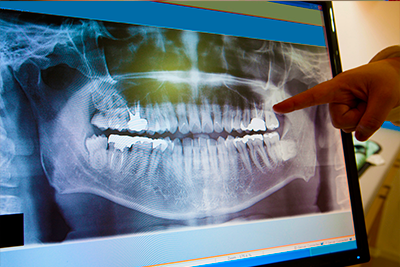

Contamos con radiografías convencionales y digitales que permite detectar cualquier problema que presente el paciente, consiguiendo una mayor comprensión de la estructura dental así como una prevención efectiva de problemas futuros, brindando de esta manera una diagnóstico completo al paciente.